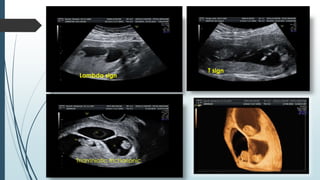

CHORIONICITY : The accurate determination of chorionicity is

fundamental for successful management of twin pregnancies

A distinct thickening of the dividing membrane (โ€œlambdaโ€orโ€œtwin peakโ€ sign)

represent dichorionic (DC)

Thin, โ€œT-shapedโ€ insertion of the membrane into the placental surface is

indicative of monochorionic placentation.

In monochorionic/diamniotic gestations, the risk of developing twin-to-twin

transfusion syndrome (TTTS) later in pregnancy may be estimated by

1) measuring the NTโ€™s (the likelihood of TTTS increases with increasing

difference in the NT measurements between the two fetuses)

2)evaluating the ductus venosus with Doppler (presence of reversed a-

wave increases the riskof TTTS)

3) Assessing the vascular connection in placenta via doppler

First trimester ultrasound screening is the only best option to detect

aneuploidy in multifetal gestation because serum markers are not valid.

Lambda sign

T sign

Triamniotic trichorionic